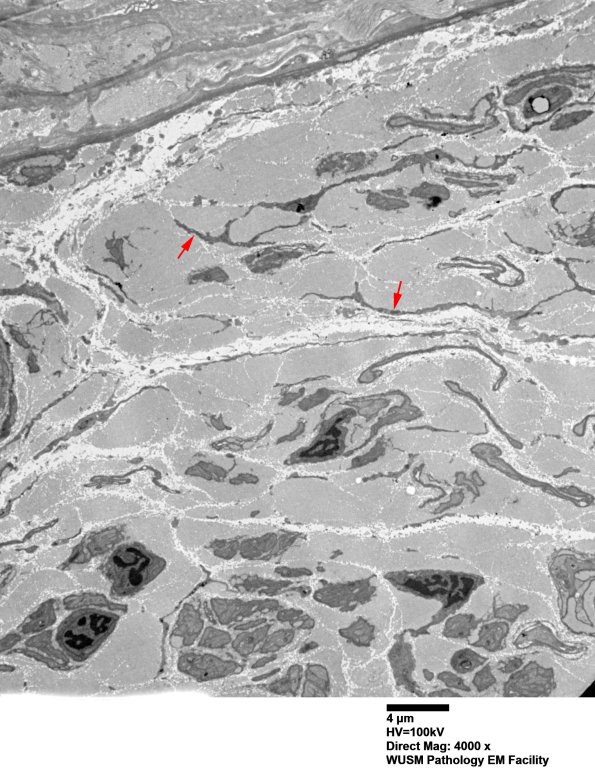

The extensive course of neuropathy in this patient has resulted in the marked increase in endoneurial collagen, loss of many typical bands of Büngner and the proliferation of delicate, questionably atrophic cellular processes (arrows). The atrophic processes likely reflect remote bands of Büngner and/or delicate fibroblast processes which may be difficult to separate even with ultrastructural examination. (electron micrographs)